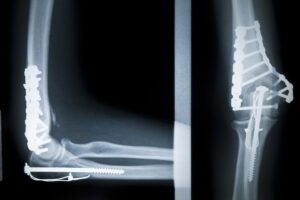

Ellbogengelenksfrakturen

Die chirurgische Versorgung von Ellbogenfrakturen ermöglicht eine exakte Wiederherstellung der Gelenkfunktion und verhindert langfristige Bewegungseinschränkungen.

Distale Humerus-Fraktur

Die Behandlung von distalen Humerus-Frakturen erfordert höchste Präzision, um die Beweglichkeit des Arms nachhaltig zu sichern und Schmerzen zu reduzieren.